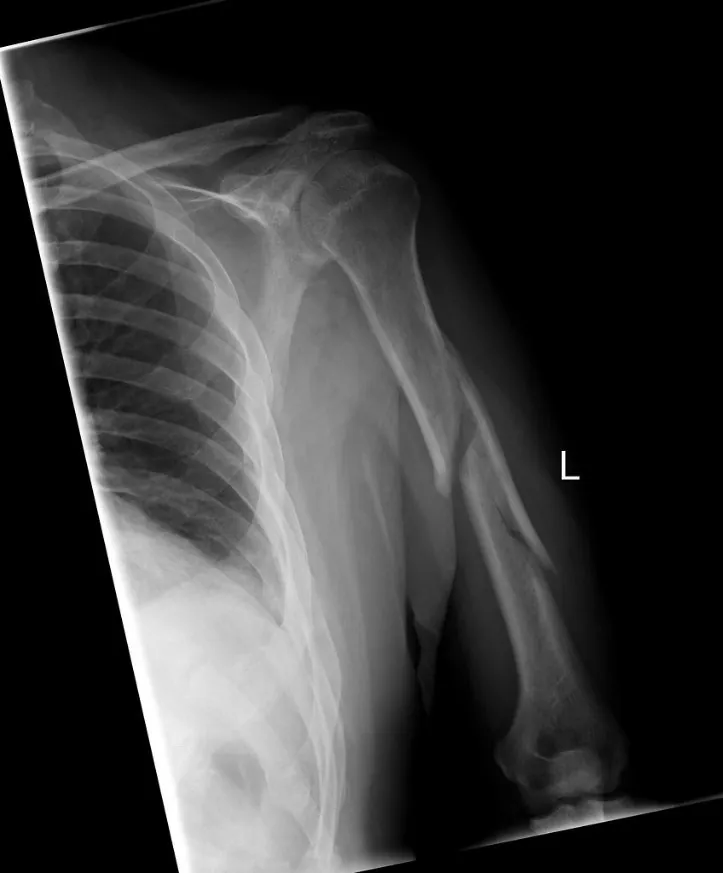

Humeral shaft fractures involve the midsection of the humerus bone, which connects the shoulder joint to the elbow joint. These fractures can range from simple to complex, depending on the severity of the injury. Patients may experience pain, swelling, bruising, and difficulty in moving the arm after such fractures.

The humeral shaft locking plate is an implant designed to provide stable fixation for humeral fractures. It is constructed with a locking mechanism that securely holds screws in place, ensuring better bone-to-plate interface and enhanced stability during the healing process.

During the surgical procedure, the orthopedic surgeon carefully aligns the fractured bone fragments and secures the locking plate over the fracture site. Specialized screws are inserted through the plate and into the bone, creating a rigid construct that allows early movement and faster healing.